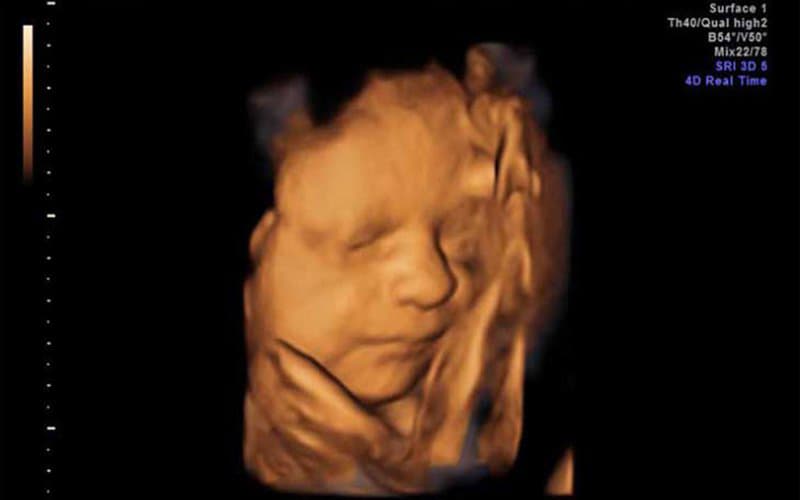

Tại tuần 29, thông qua việc khám thai, mẹ có thể biết được sự phát triển rõ ràng của bé.

Nhiều ba mẹ rất tò mò không biết hình dáng của thai nhi 29 tuần tuổi phát triển như thế nào.